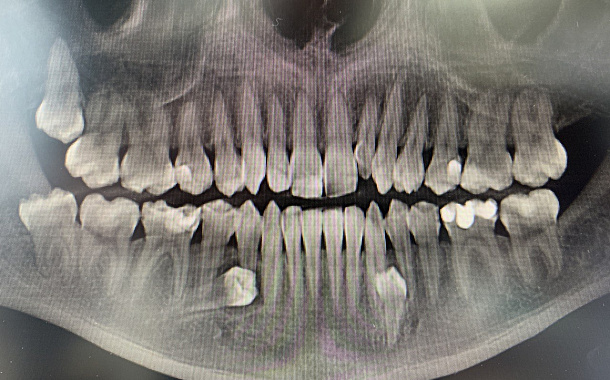

Применение Indiba после стоматологических процедур, таких как удаление зубов, костная пластика и имплантация, обеспечивает ряд значительных преимуществ:

- Ускоренное заживление: за счет стимуляции клеточной активности способствует более быстрому восстановлению тканей.

- Уменьшение отека и боли: улучшение микроциркуляции помогает снизить послеоперационный отек и болевые ощущения.